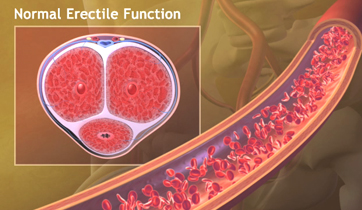

Erectile Dysfunction

Medtronic Corporation

This animationis intended to explain Erectile Dysfunction to physicians. It shows the vessels and nerves involved in blood flow obstruction to the penis, and the erectile tissue's failure to enlarge. The animation also suggests the benefits of clearing the obstruction by using stents.